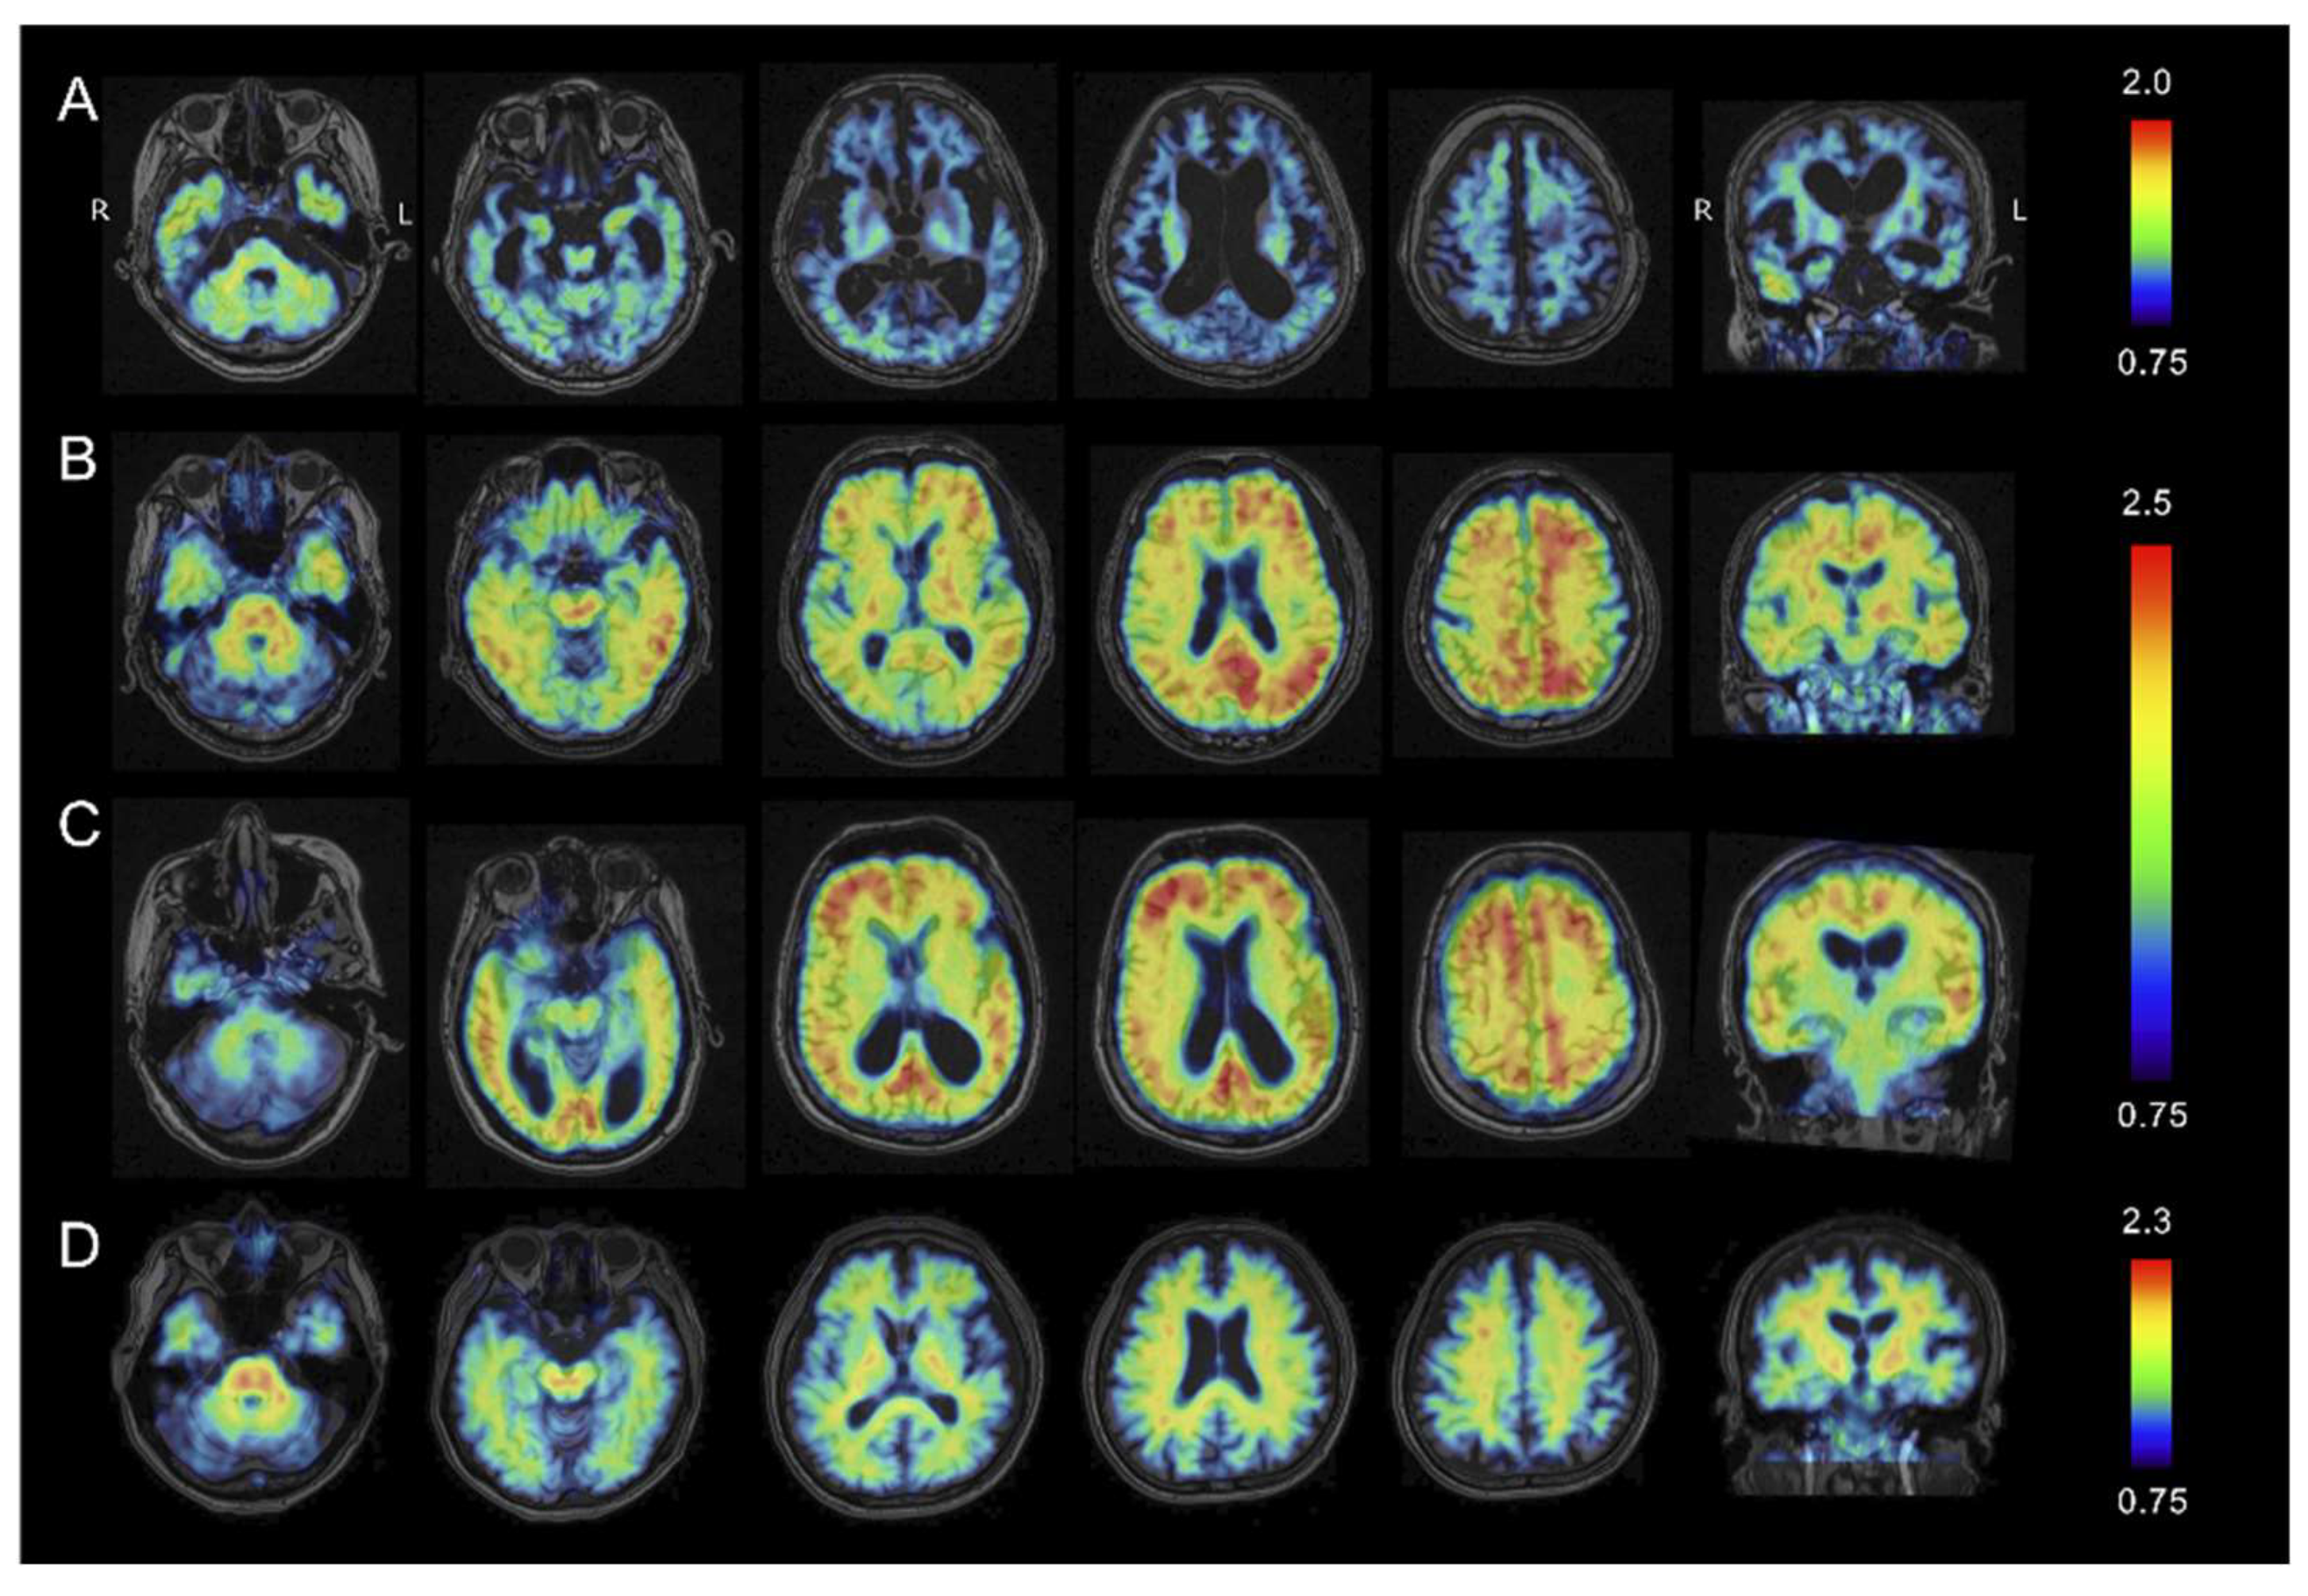

2.4. Amyloid β PET Imaging